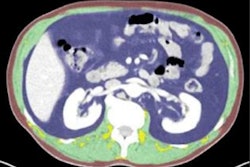

In other ultrasound news, a group from Australia believes that the recent shortage of iodinated contrast for CT studies offers an opportunity to use ultrasound and MRI instead. And ultrasound can be helpful in guiding interventional cardiology procedures, says a group from Canada.